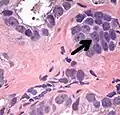

Intraductal carcinoma

Intraductal carcinoma of the prostate gland (IDCP), which is now categorised as a distinct entity by WHO 2016, includes two biologically distinct diseases. IDCP associated with invasive carcinoma (IDCP-inv) generally represents a growth pattern of invasive prostatic adenocarcinoma while the rarely encountered pure IDCP is a precursor of prostate cancer.[20] The diagnostic criterion of nuclear size at least 6 times normal is ambiguous as size could refer to either nuclear area or diameter. If area, then this criterion could be re-defined as nuclear diameter at least three times normal as it is difficult to visually compare area of nuclei.[20] It is also unclear whether IDCP could also include tumors with ductal morphology.[20] There is no consensus whether pure IDCP in needle biopsies should be managed with re-biopsy or radical therapy. A pragmatic approach would be to recommend radical therapy only for extensive pure IDCP that is morphologically unequivocal for high-grade prostate cancer.[20] Active surveillance is not appropriate when low-grade invasive cancer is associated with IDCP, as such patients usually have unsampled high-grade prostatic adenocarcinoma.[20] It is generally recommended that IDCP component of IDCP-inv should be included in tumor extent but not grade.[20] However, there are good arguments in favor of grading IDCP associated with invasive cancer.[20] WHO 2016 recommends that IDCP should not be graded, but it is unclear whether this applies to both pure IDCP and IDCP-inv.[20]

-

Intraductal carcinoma of the prostate with an infiltrative growth pattern may be morphologically difficult to distinguish from invasive cancer. One focus shows comedonecrosis (arrow), morphologically suggesting Gleason pattern 5 invasive carcinoma (a haematoxylin and eosin, b CK5/6)[20] -

Intraductal carcinoma of the prostate with very patchy basal cells identified by immunohistochemistry. At least some of the glands lacking basal cell immunoreactivity represent intraductal rather than invasive carcinoma (a haematoxylin and eosin, b CK 5/6)[20]